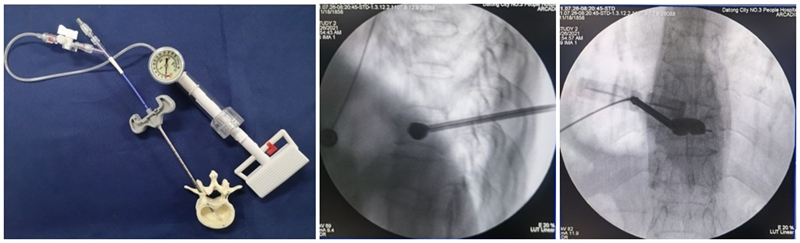

(6)注入骨水泥:应用骨水泥灌注管灌注骨水泥时,由聚醚醚酮树脂制成的灌注管在骨水泥灌注完成后要及时拔除,避免椎体内骨水泥硬化后无法拔出;椎体穿刺侧骨水泥灌注不满意,可拔除输送套管,直接连接穿刺套管,进行二次灌注。

术后行影像学检查,显示骨水泥弥散满意,达到了单侧穿刺,双侧弥散的效果,无渗漏